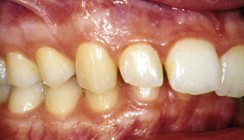

Die Fotostatusaufnahmen zeigen den erschwerten Mund- und Lippenschluss in der zentrischen Relation. Im Gesicht ist die Unterkieferabweichung nach rechts zu sehen (Abb. 1a–c). Der Fotostatus von lateral zeigt ein Rückgesicht schräg nach vorne und im Vergleich zum Mittelgesicht ein langes Untergesicht (Tab. 1). Der Patient hatte eine Klasse III-Dysgnathie mit mandibulärer Mittellinienverschiebung nach rechts, einen zirkulären Kreuzbiss (Abb. 2a–e). Im Oberkieferzahnbogen bestand Nichtanlage der Zähne 12 und 22 sowie Lücken in der Front. Der Engstand im Unterkiefer betrug 3 mm. Als Kompensation der skelettalen Dysgnathie trat eine linguale Kippung der Unterkieferfront ein.

Die intraoralen Bilder zeigen die Situation nach der Behandlung (Abb. 6a–f). Es wurden stabile funktionelle Okklusionsvehältnisse auf beiden Seiten und harmonische Zahnbögen hergestellt. Die Lücke zwischen den Zähnen 11 und 21 wurde mit Kompositmasse geschlossen. Die Eckzähne wurden anstelle der seitlichen Schneidezähne ohne Formveränderung eingestellt Die extraoralen Aufnahmen lassen eine harmonische Gesichtsdrittelung in der Vertikalen und ein harmonisches Profil in der Sagittalen erkennen. Das Mundprofil ist harmonisch bei entspanntem Lippenschluss (Abb. 7a–c). Funktionell lagen keine Einschränkungen bei den Unterkieferbewegungen vor (Tab. 1).